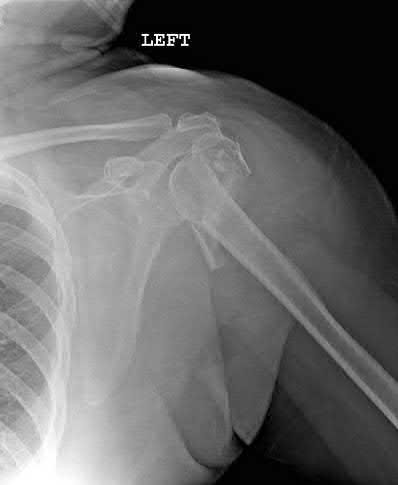

A 70-year-old woman falls down a flight of stairs and sustains the injury shown in Figures A and B to her dominant upper extremity. She lives alone and has no other medical history. Which of the following surgical options is best to minimize complications for this fracture pattern?

This patient has a complex proximal humerus fracture with metaphyseal comminution and poor bone stock. Cemented reverse total shoulder arthroplasty (rTSA) using a long stem prosthesis and tuberosity repair is indicated.

Proximal humerus fragility fractures are hard to treat because of comminution and poor bone stock. AVN is common with glenohumeral fracture-dislocation. Hemiarthroplasty (and standard total shoulder arthroplasty, TSA) is unreliable because of dependence on tuberosity healing. rTSA is recommended for fractures in patients >70 years with severely comminuted fractures, high likelihood of head AVN, and poor tuberosity bone quality (osteoporosis or comminution).

Bufquin et al. retrospectively reviewed the use of rTSA for treatment of 43 patients with 3- and 4-part proximal humerus fractures. They found satisfactory elevation (97°), ER in abduction (30°), constant scores (44) and modified Constant scores (66%). Complications included calcification (90%), tuberosity displacement (53%) and scapular notching (25%). They concluded that rTSA was a good procedure because it provides pain relief and easier functional recovery in spite of failed tuberosity healing.

Anakwenze et al. systematically reviewed acute proximal humerus fractures. Frequency weighted range of motion was flexion 122°, abduction 97°, ER at neutral 18°. Tuberosity repair yielded higher ER compared to no repair.

Scapular notching was the most common complication (32%). They concluded that rTSA patients tended to be elderly women with 4-part fractures, had good pain control but residual dysfunction.

Jobin et al. reviewed rTSA for management of proximal humerus 3- and 4-part fractures. They note >50% of cases have tuberosity resorption. They recommend repairing the greater tuberosity to restore infraspinatus/teres minor function which improves external rotation strength. Greater tuberosity malunion is not a result of secondary displacement, but rather, from intraoperative malreduction. Lesser tuberosity repair should be performed if there is significant bone loss or intraoperative anterior instability.

Figures A and B are AP radiograph and 3D reformatted CT scan showing comminuted proximal humerus fracture dislocation. Illustration A shows rTSA performed with distal cementation of a long stem prosthesis and cerclage fixation of the proximal shaft and the tuberosity fragments.

Incorrect Answers:

Answer 1: ORIF has potential complications of screw cut out, AVN, fracture collapse, tuberosity resorption and loss of fixation. The risk of AVN (and resultant screw cut out) is high because of comminuted fracture-dislocation. Answer 2: Cementing is indicated because metaphyseal fracture bone loss compromises stem fixation.

Answer 3: Greater tuberosity repair improves external rotation strength. Lesser tuberosity repair adds to anterior stability.

Answer 5: Proximal humeral replacement is only necessary for tumor or unreconstructable fractures. They have poorer outcomes because of loss of rotator cuff function.